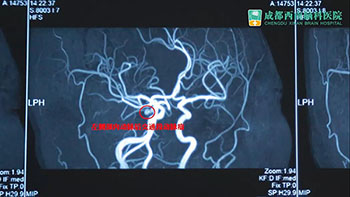

晏女士在医生的建议下,转入我院寻求黄光富教授的治疗。经检查,发现她左侧眼睑下垂,不能自己睁开。扒开眼皮,左瞳孔放大,对光反射消失,眼球偏外,且不能正常转动。头颅MRA检查后,确诊为左侧颈内动脉后交通段动脉瘤,拟行动脉瘤夹闭手术。

术前影像学检查